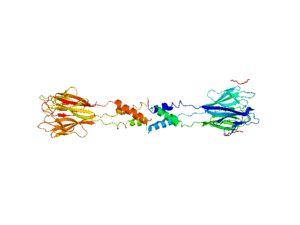

Therefore, the researchers in this study aimed to comprehensively profile cytokine immune responses in individuals with ME/CFS. They recruited 192 ME/CFS patients and 392 controls who did not have the condition. They measured serum cytokine levels in all the participants. Age, sex and race of participants were all taken into consideration. The researchers found that TGF-β (primarily secreted by regulatory T cells) was elevated in individuals with ME/CFS and resistin (primarily secreted by peripheral blood mononuclear cells) was lower. 17 cytokines altogether were correlated with the severity of ME/CFS including IFN-γ, IL-4, IL-5 and CXCL1 . Thirteen out of these seventeen cytokines had pro-inflammatory functions and may be the cause of the symptoms experienced by ME/CFS patients.